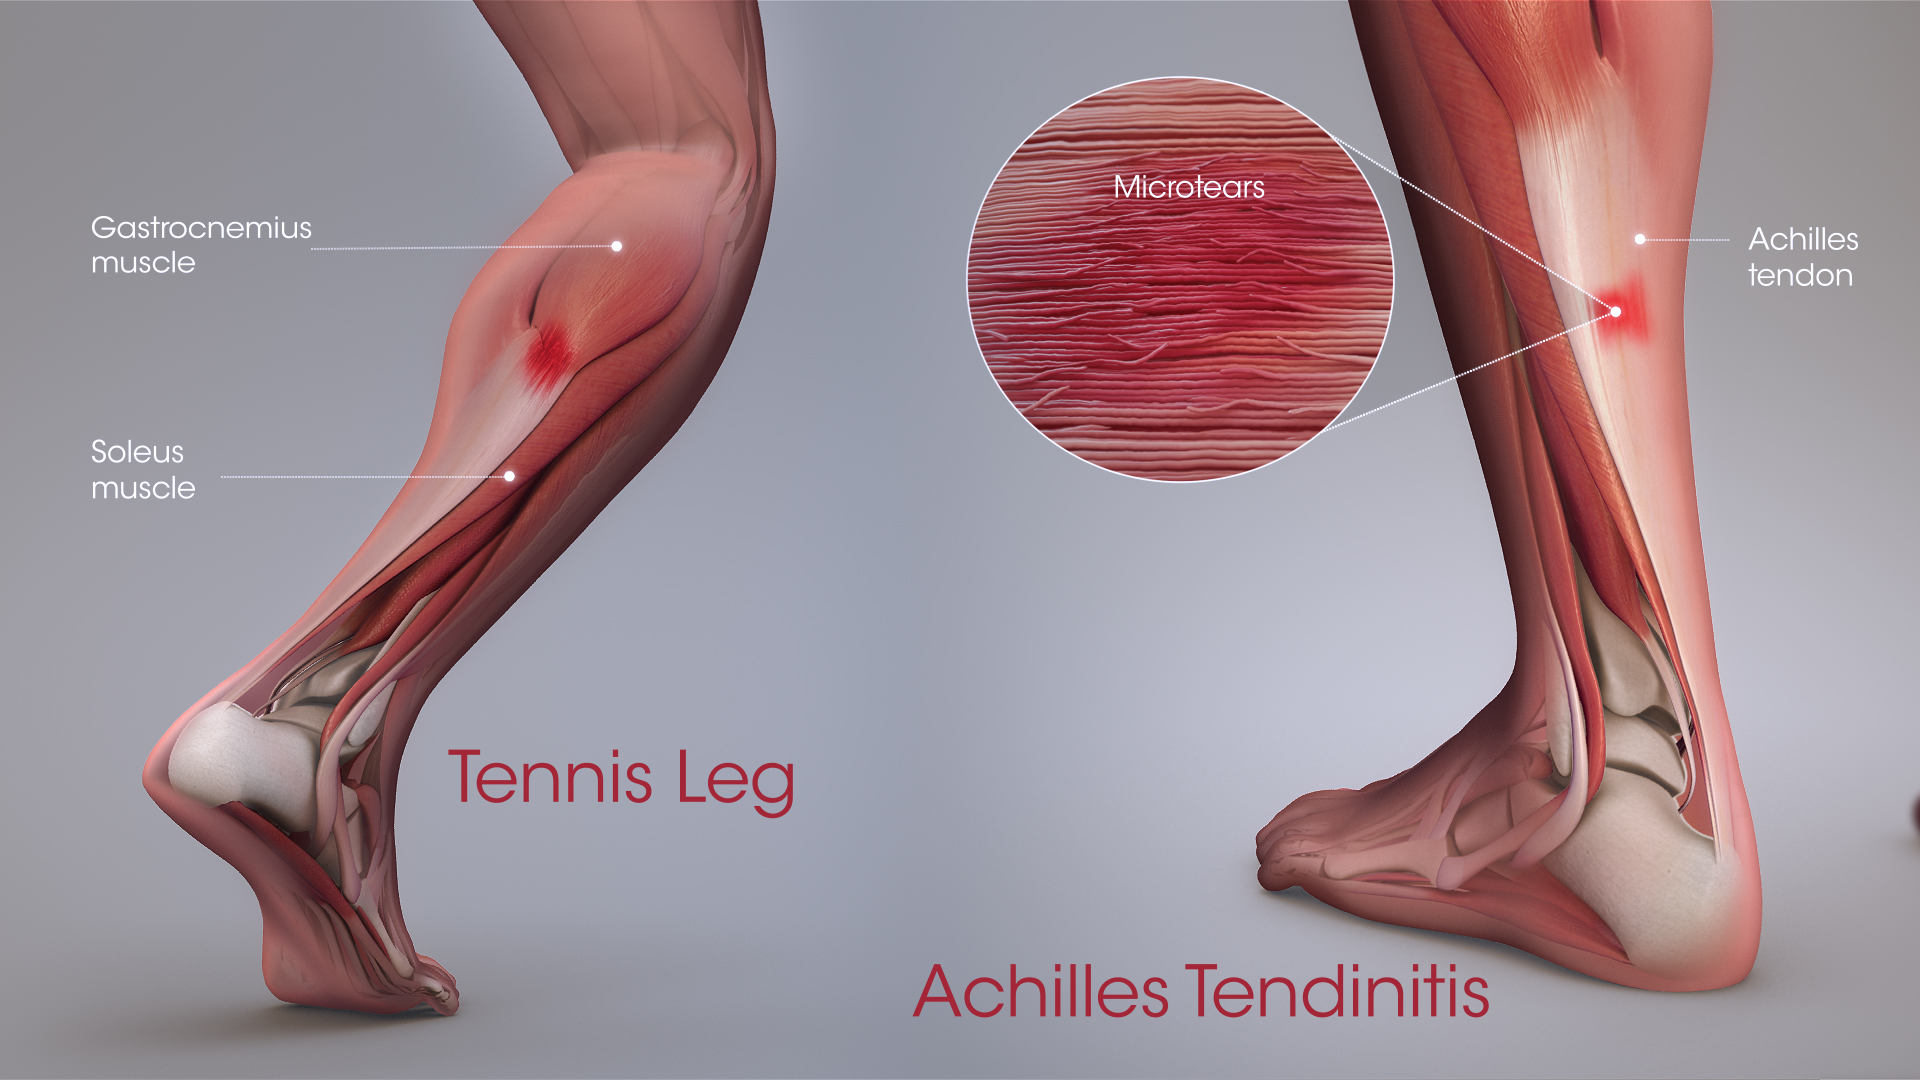

Тендинит Ахиллова сухожилия: симптомы и лечение

Раздел: Картинки на заметку